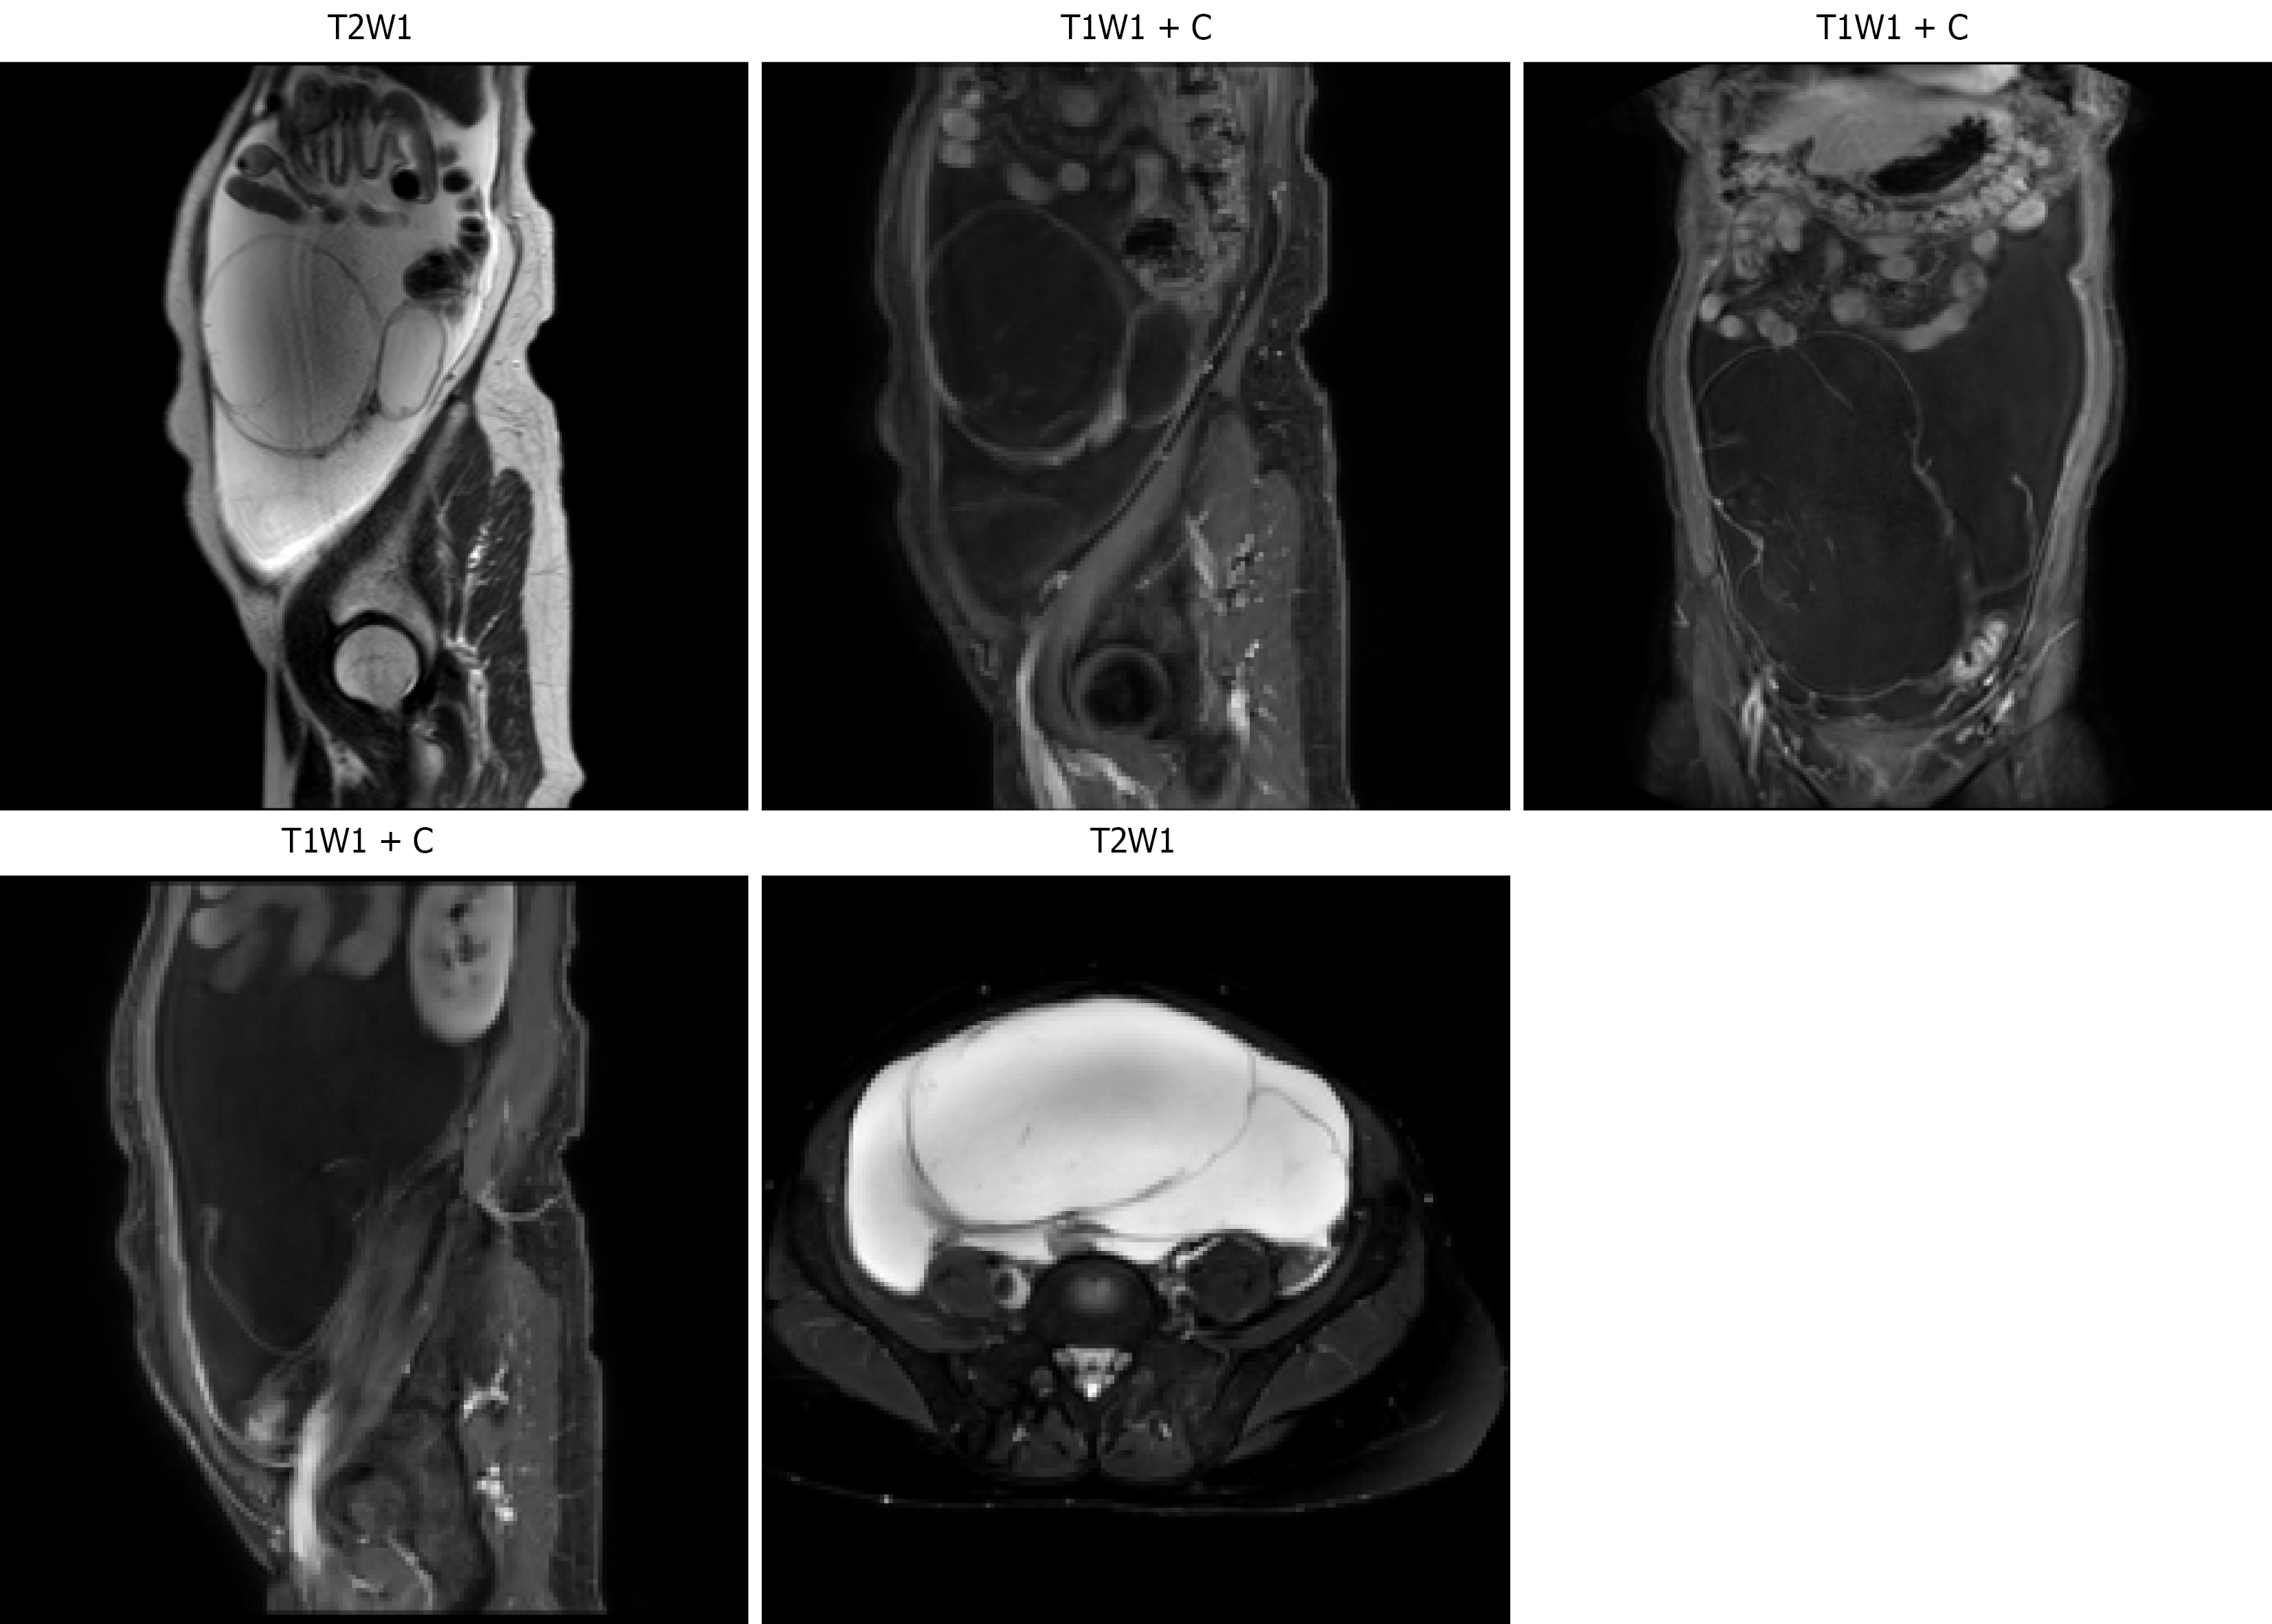

Figure 3 Magnetic resonance imaging shows the lesion before treatment.

T2W1: T2 weighted imaging; T1W1: T1 weighted imaging; T1W1 + C: T1 weighted imaging with contrast.